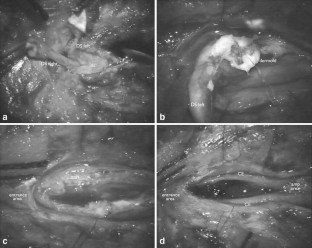

Cases of infected dermal sinus are scarce and detailed surgical anatomical descriptions are hardly found in literature. The clinical, radiological, and surgical findings in four cases of an infected dermal sinus located at the lower spine are presented to elucidate the pathological anatomical configuration.

The first case showed two dermal sinuses with a parallel course extra- and intradurally, ending in a confluence of cavities connected to the conus. In this case, as well as in the fourth case, the signs and symptoms were those of meningitis. The second case presented with meningitis and a subdural empyema, while the third case presented with an intradermoid–intramedullary abscess at the junction between the DS and the conus. This child probably showed signs and symptoms of conus involvement as early as during pregnancy.

The anatomy of the nervous elements in this congenital anomaly is heavily disturbed, more particularly in case of infection, due to extensive arachnoidal scarring. The latter renders dissection laborious and recognition of anatomical details difficult, resulting in complete excision of a dermal sinus in less than half of the cases. Despite their variability in presentation, most cases of an infected dermal sinus show similar characteristic features.